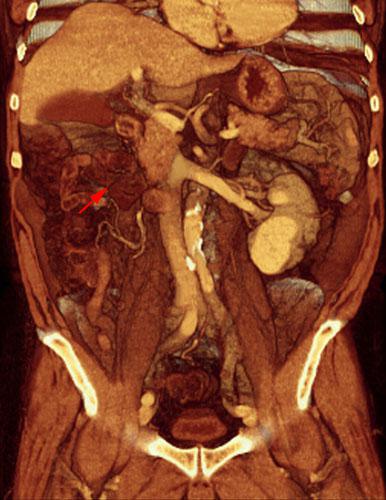

Recidiva adenopática de hipernefroma